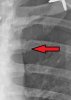

Xrays

do you have a cracked rib as well james? in series 2 it looks like one is cracked.

Are you talking about this?